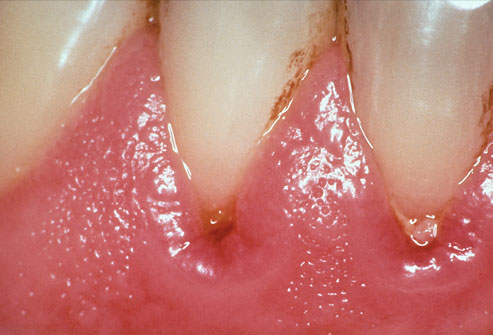

На фото симптомы гингивита воспаление десен

Острый гингивит проявляется болью, усиленным слюноотделением, неприятным запахом изо рта. Хронический гингивит проходит медленно, для него характерны кровоточивость, синюшность и разрыхление десен.